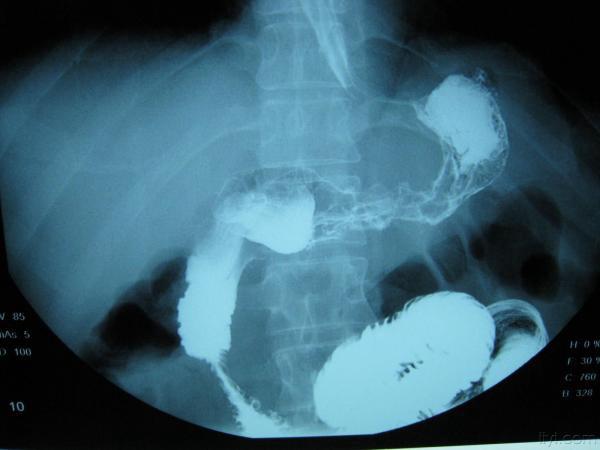

典型皮革胃!!!!

刚收一典型的皮革胃,准备明天腔镜下全胃切除,这个造影做的不错,希望对大家有帮助,只是照的不太好,见谅!!!

简单介绍一下皮革胃 皮革胃可以说是胃癌的一种,生长方式主要还是浸润式生长,最后使胃失去功能,使胃缩小,质地硬,像皮革一样,有称呼为革囊胃 临床上表现 1症状早期表现为上腹不适 2晚期可以摸到胃部 隆起 3贫血、消瘦、腹水等等!~ 检查: X线检查,造影 纤维胃镜, CT 细胞脱落病理检查 治疗: 手术行胃Ca 根治术 化疗 肠道营养 说的不太详细,以书本为主吧